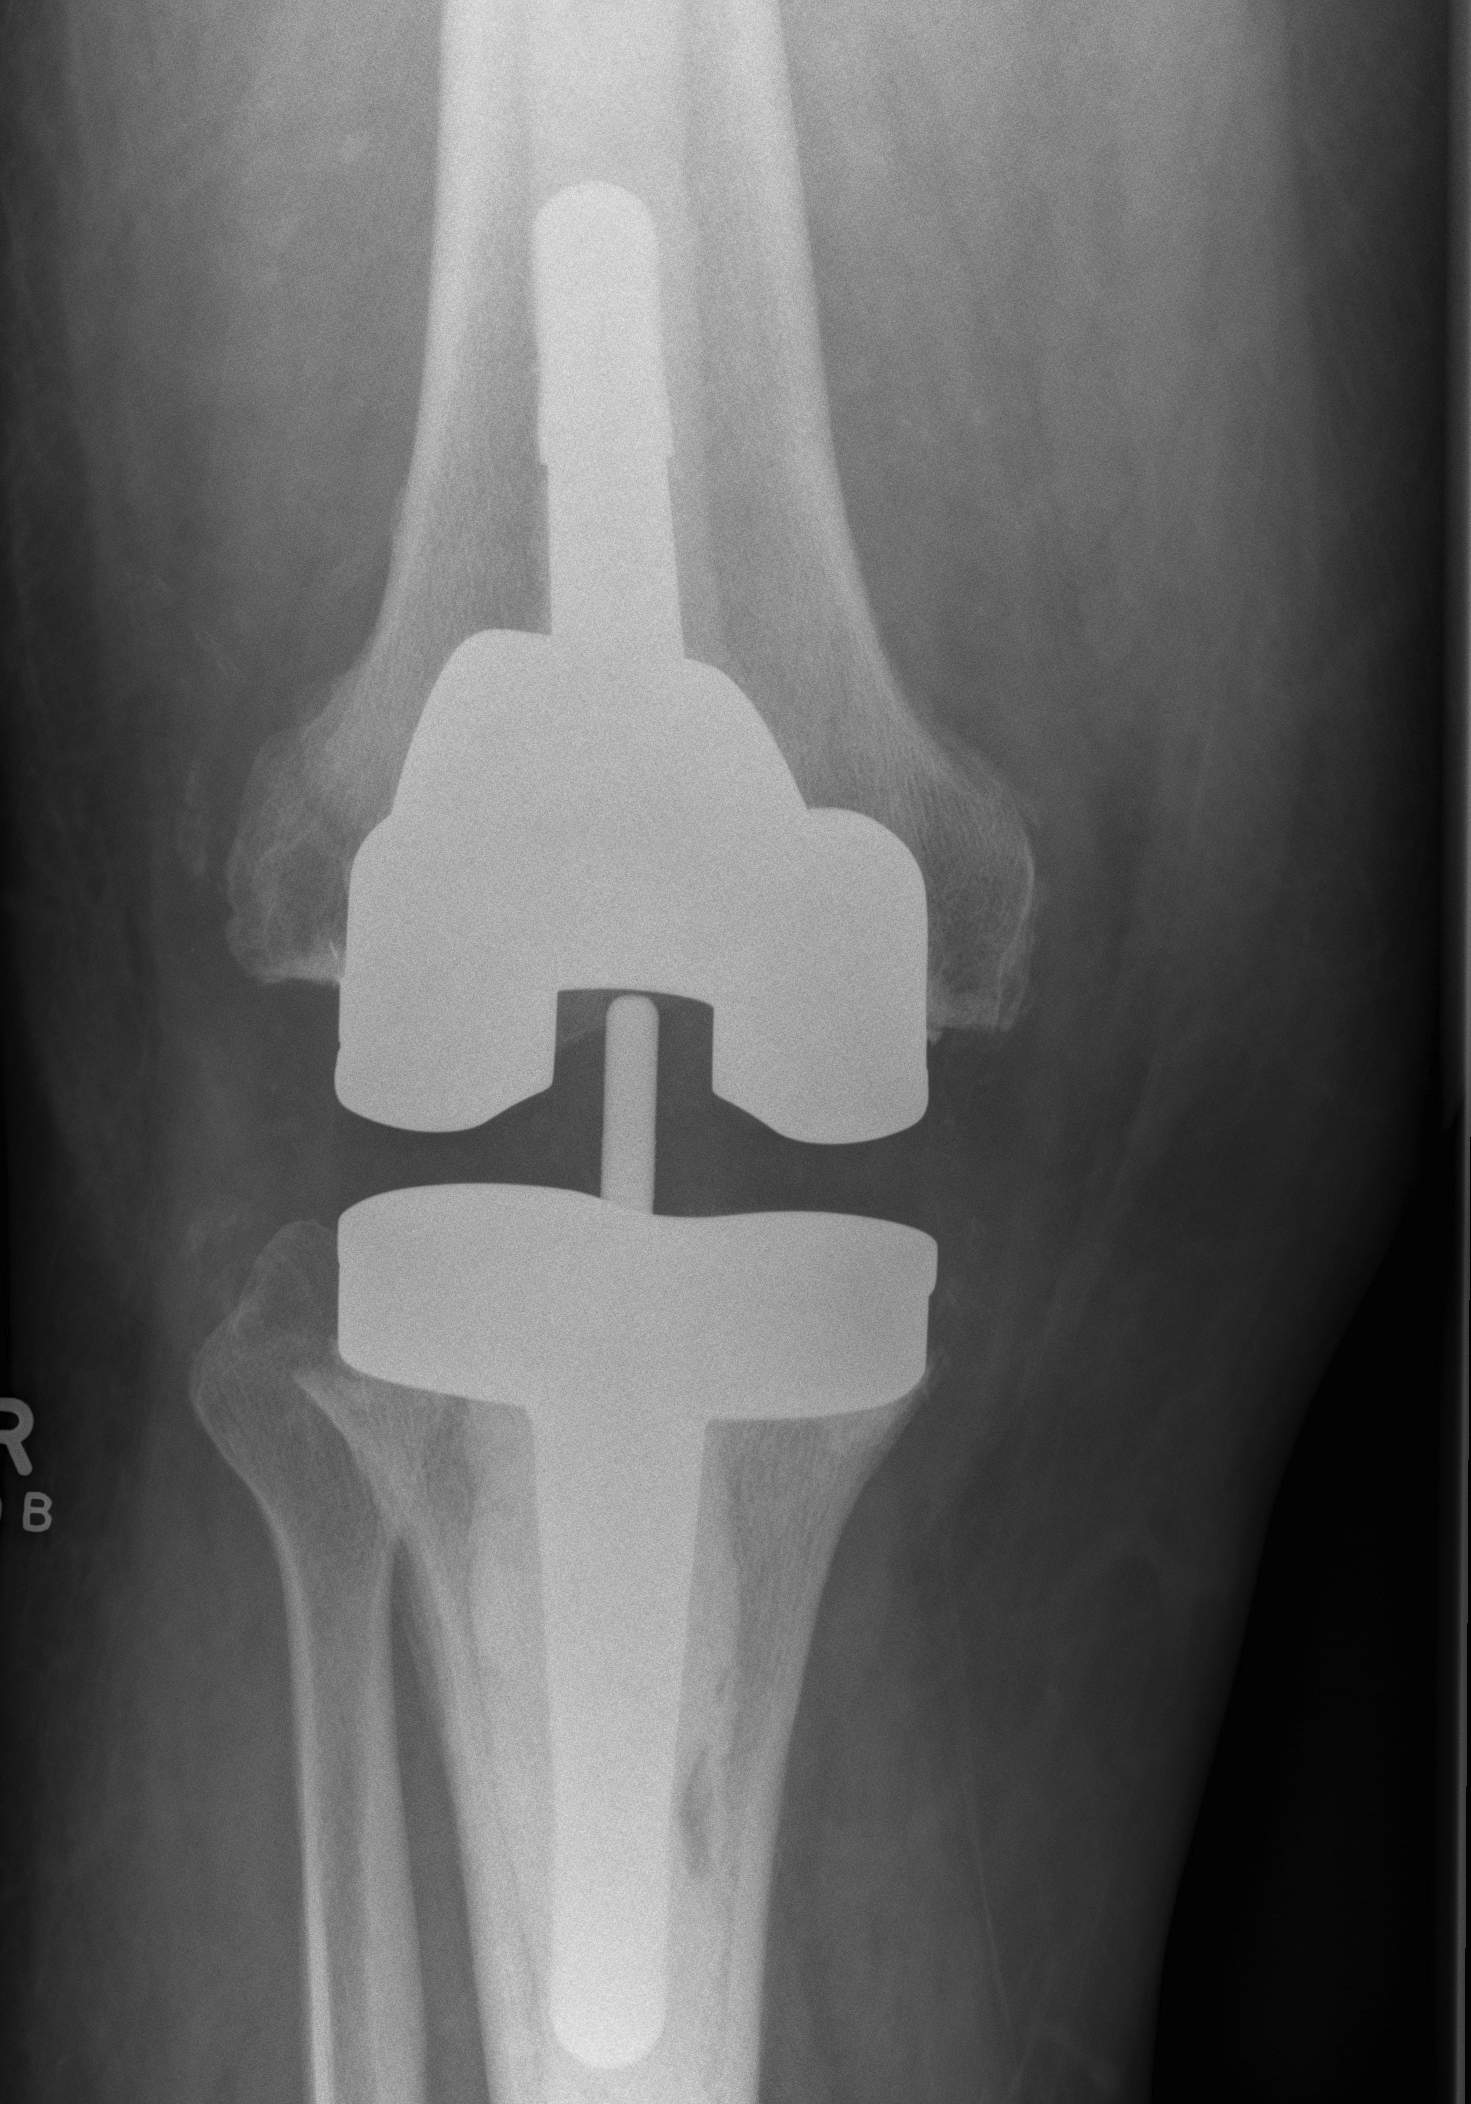

3. Constrained Hinged / Rotating Hinged

Design

1. Uniplanar hinge

- prohibited rotational motion

- high rate of aseptic loosening

- historical

2. Rotating Hinge

- linked with an axle

- restricts varus-valgus and translation

- permit rotation of the tibial bearing about a yoke on the tibial platform

- again need long stems to disperse forces